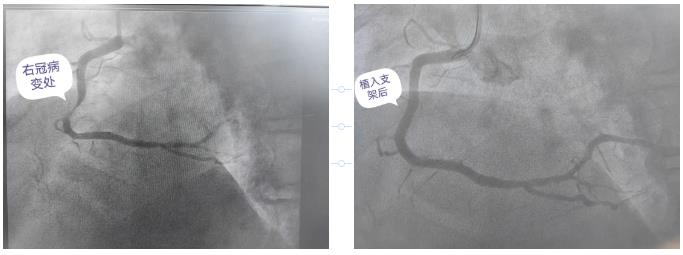

凌晨三点,急诊抢救室的红灯骤然亮起。一位急性心肌梗死患者被救护车紧急送抵,心电图显示ST段抬高,情况危急。心血管病科主任胡友斌迅速带领团队启动应急预案,导管室的灯光瞬间照亮了寂静的走廊。消毒、铺巾、穿刺、造影……

一系列操作行云流水,在与时间的赛跑中,支架成功植入堵塞的血管,患者的生命体征逐渐平稳。当监护仪上的数据趋于正常时,窗外已泛起微光,胡主任摘下沾满汗水的口罩,露出了欣慰的笑容。